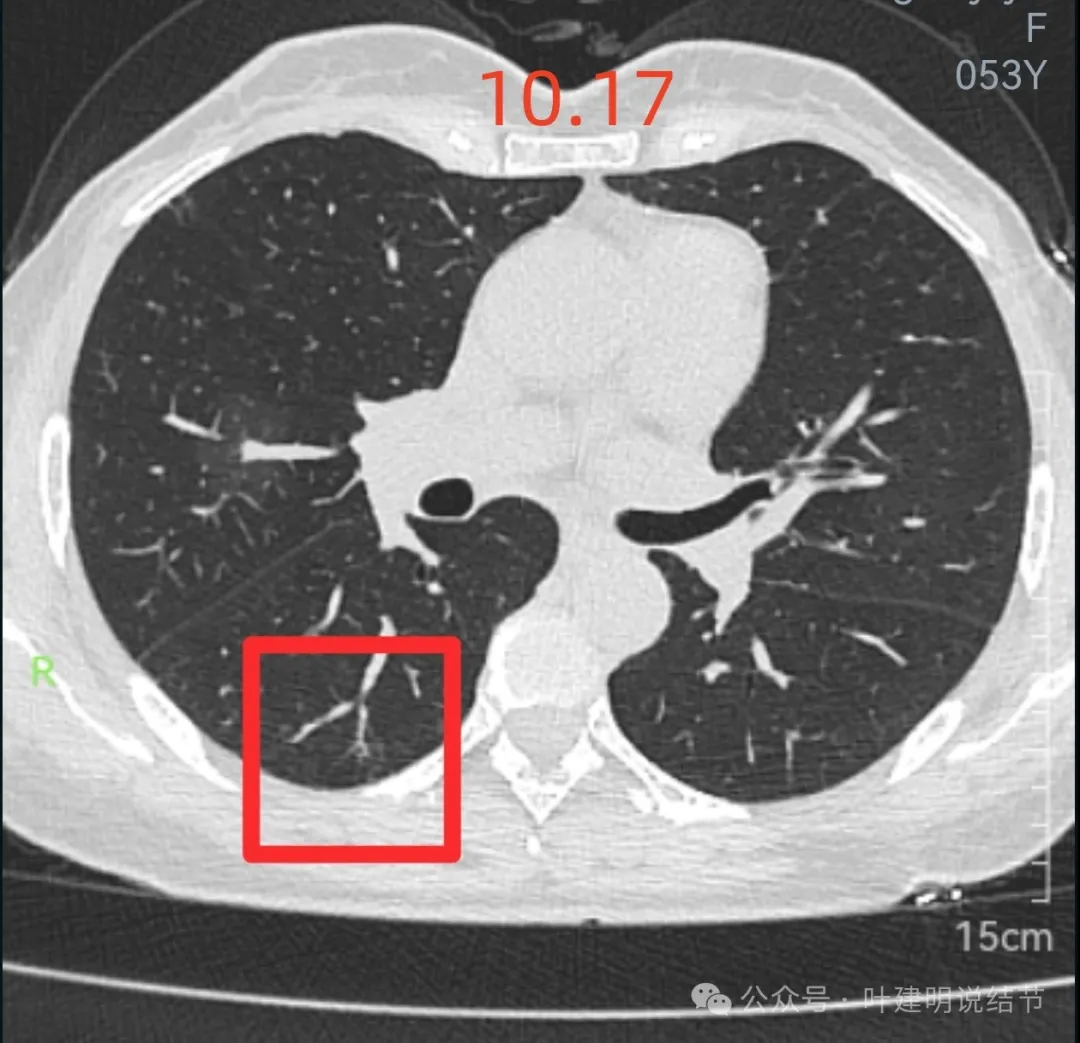

先来看2024年10月16日的影像:

右下叶背段边界欠清的磨玻璃影,有血管刚好位于病灶处。

右下叶以及左下叶实性结节,缺乏膨胀性,没有收缩力,紧贴胸壁或膈肌无牵拉凹陷。

再来看周教授认为4B类的右上后段病灶连续层面影像信息:

边缘区域离叶间裂更近,仍无牵拉。

几乎贴着叶间裂了,仍无任何牵拉影响。

病灶密度边缘部分也不均,离叶间裂近而没有影响。

上图病灶已经贴着叶间裂,但仍显示是平直的,没有任何牵拉影响。

矢状位上看,病灶虽整体轮廓较清,但瘤肺边界显模糊,整体不致密。

冠状位上看病灶有实性成分,实性成分缺乏收缩力,外围是淡磨玻璃成分,瘤肺边界欠清,贴着叶裂没有影响。

从连续层面以及影像细节上看,这个病灶就不可能是恶性的!短期内出现,混合密度而瘤肺边界不清,整体缺乏收缩力也无膨胀性,灶内实性成分不致密且磨玻璃成分过淡,灶内血管有异常增粗与密度过高,又是两肺多发病灶。这所有的表现与病情发展都与感染性病变契合,周围淡磨就是炎症水肿的关系,血管异常就是管壁有炎症的关系,多发就是感染(致病因素)影响两肺的关系。怎么可能是恶性?